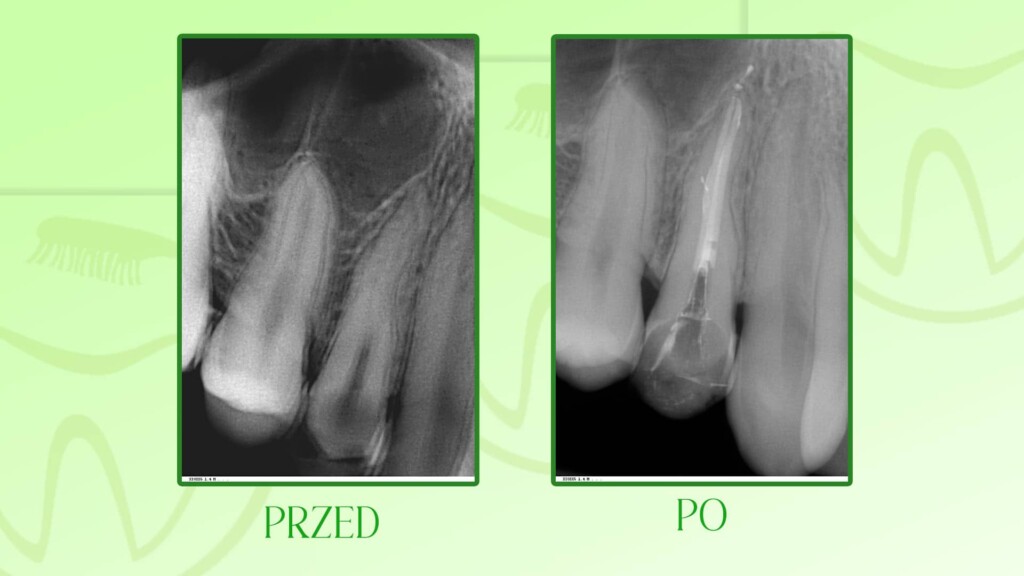

Poniżej prezentujemy wybrane prace leczenia kanałowego zębów wykonane w naszym gabinecie dentystycznym Unident w Szczecinie